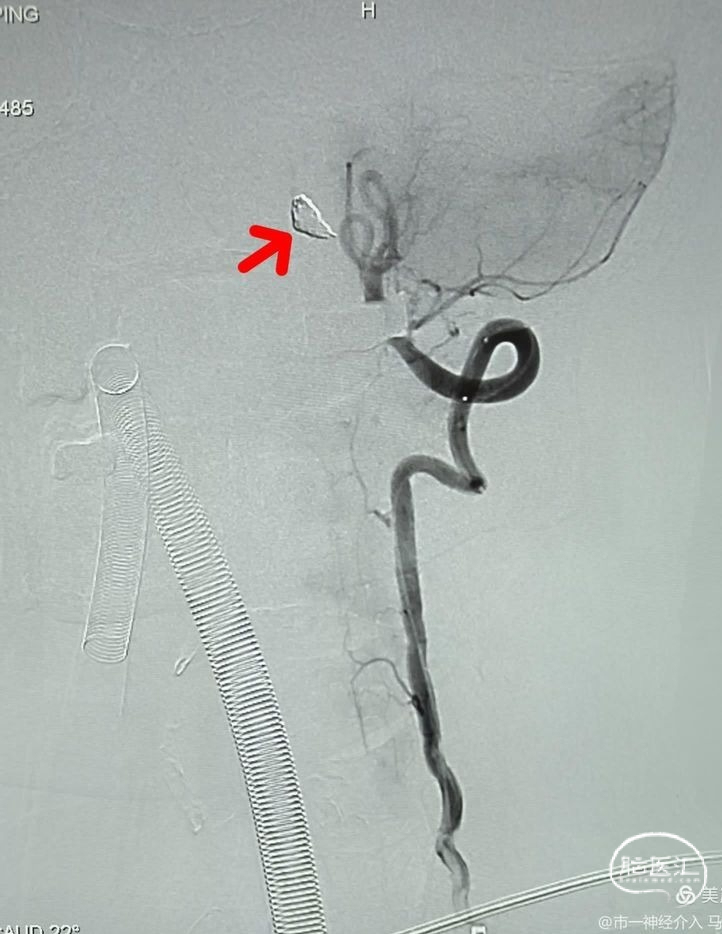

考虑到动脉瘤累及到血管的一周,既血管壁的一圈,而小脑后下动脉距离病变有相当长的距离,且对侧椎动脉发达,基底动脉的供血不成问题,所以果断决定闭塞载瘤动脉及动脉瘤,以绝后患。

手术方案一旦形成,操作就变得非常简单,微导丝携带微导管很快到达动脉瘤腔。

选择合适的弹簧圈填塞动脉瘤腔,调控微导管的张力,让弹簧圈分布尽量均匀一些。

两枚弹簧圈填塞后造影,见载瘤动脉仍通畅,这种情况仍然有复发并再出血的风险。

继续填塞弹簧圈,瘤体近端约2mm的血管一并栓塞做成“塞子”。

数枚弹簧圈进去,载瘤动脉及动脉瘤致密栓塞,小脑后下动脉显影良好,且有侧支与基底动脉近端联通。